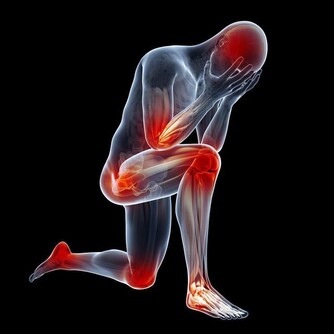

5. 脊髓型:是頸椎間盤突出或者骨贅壓迫到了脊髓,常見症狀有上下肢無力感,逐漸出現走路踩棉花感,步態拙笨甚至跌倒。後期還可出現排二便障礙。

由上可知,頸椎病的表現形式可以多種多樣,小的突出或骨贅可能只壓迫一種組織,臨床出現症狀也少,大的骨贅可以壓迫多個組織,臨床表現也複雜。如初期為頸肩臂疼痛等神經根症狀,數年後出現頭暈、耳鳴等椎動脈或交感神經受累症狀。

很多人覺得頸椎病是小病,但是如果頸椎病嚴重的話,壓迫到交感神經影響到心臟,可以出現頸源性心髒病,出現心絞痛;壓迫到椎動脈,可能會急轉項時,引發忽然暈倒;壓迫到脊髓,猛地跌倒可能會造成脊髓的損傷,出現肢體癱瘓。這些都是可能的潛在危害。